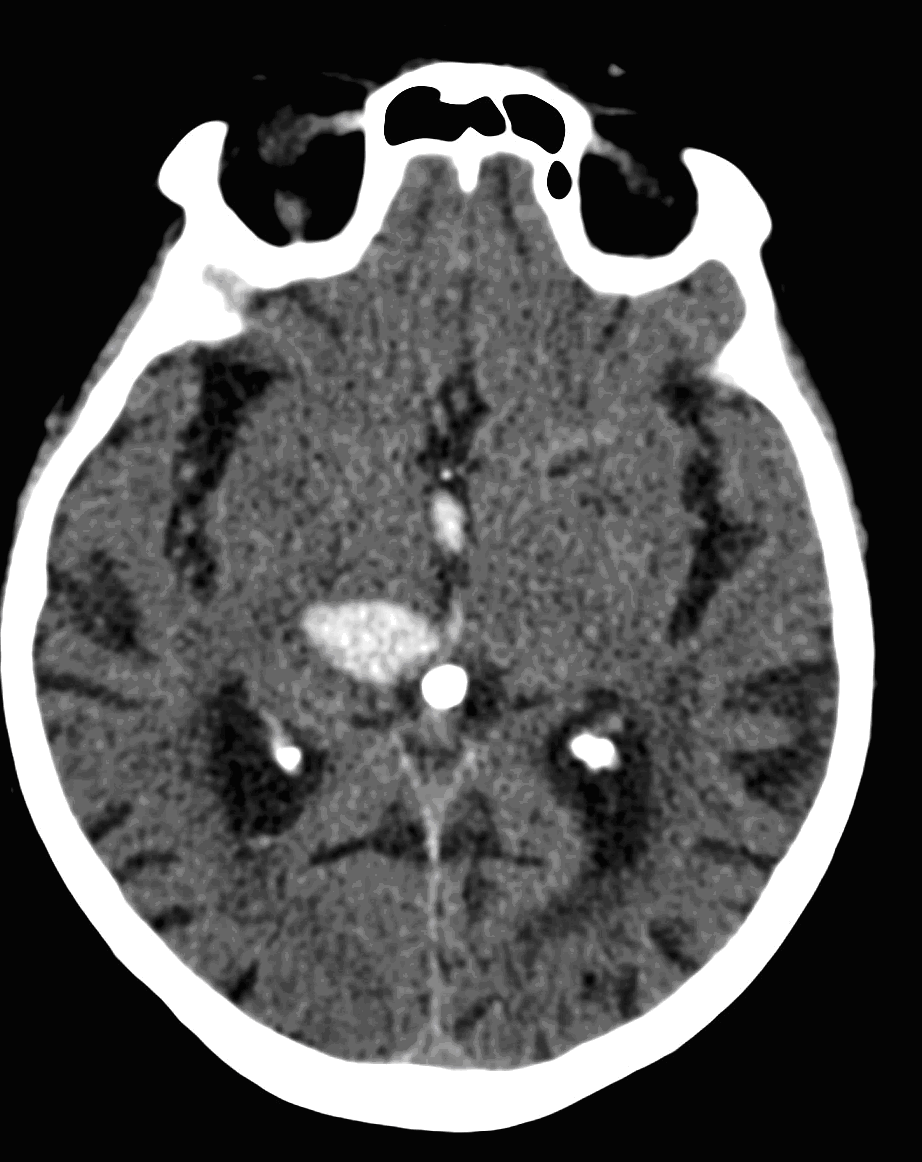

Image

11. Subarachnoid hemorrhage, CT.

Although, subarachnoid hemorrhage (SAH) is most often caused by the rupture of a berry aneurysm, arteriovenous malformation (AVM) and trauma can also lead to it. SAH is typically located at the basal subarachnoid spaces, which then propagates along the lateral fissures or it fills up the interhemispheric fissure till the convexities. The main collection of the blood is usually indicative of the source of origin. In cases of parenchymal spread the mechanism, whether it broke in, or it broke out from the parenchyma could represent a differential diagnostic challenge. When accompanied by brain edema, the consequent herniation can result in parenchymal infarcts as well.

CT angiography examination is usually advisory in order to confirm the site of the bleeding. It is also effective when a hemorrhagic tumor is in the differentials, although complete differentiation might only be achieved by follow-up examinations. CTA is also essential in the diagnostics of multiple aneurysms (which are prevalent in 20-30% of the cases based on autopsy reports.) In case of a subarachnoid hemorrhage the consequently developing hydrocephalus and its degree might only be detected on follow-up CT examinations. It is very important to note that an initial brain aneurysm rupture might be followed by a second one within the first 7 – 10 days and the resulting vasospasm carries a much higher risk of mortality than the one at the time of the first SAH. This is why the scrutonius review of the acute diagnostic imaging is essential and it plays a fundamental role in patient treatment. Open brain surgery of the aneurysm (clipping) has been replaced by catheter angiography (DSA) nowadays. The aneurysm is either filled up with thrombogenic coils through its neck or recently bypassing stents are inserted to exclude the aneurysm from the cerebral circulation.